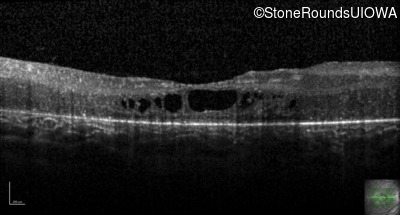

Age at visit: 17 years

This 17 year old female feels that the vision in her right eye has worsened since her cataract surgery 8 weeks ago.

Age at visit: 5 years

Age at visit: 7 years

Age at visit: 9 years

Age at visit: 11 years

Age at visit: 18 years